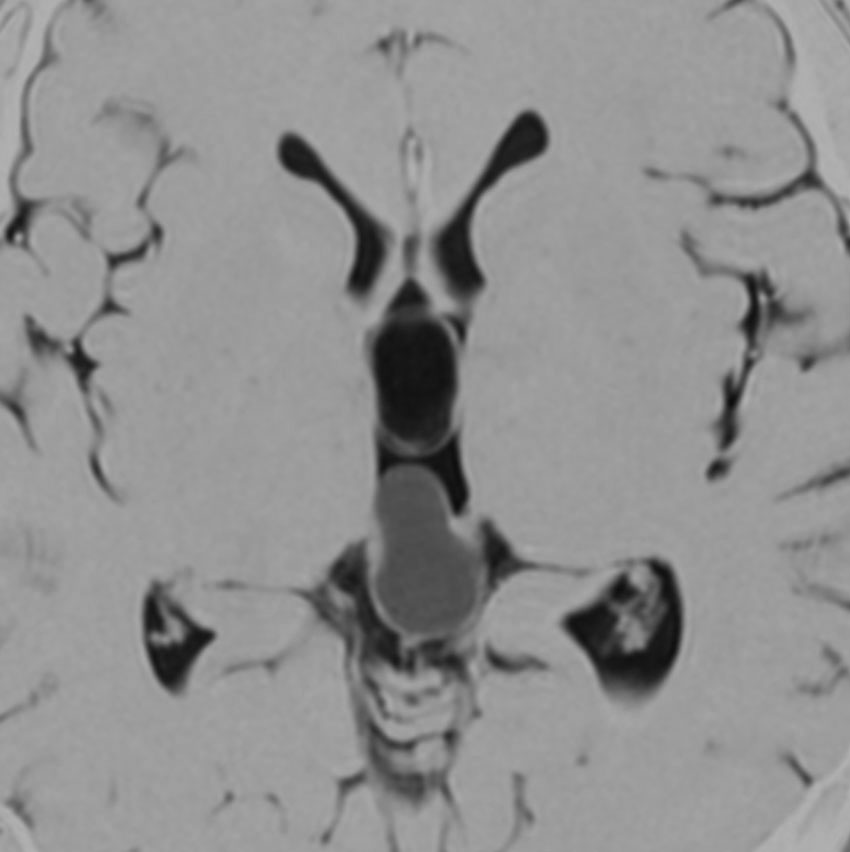

若い女性にできた,症状の全くない松果体のう胞です。右側は拡大図で,8 mmくらいの大きさでしょうか。もちろん何もする必要はありません。たくさん発見されるものです。